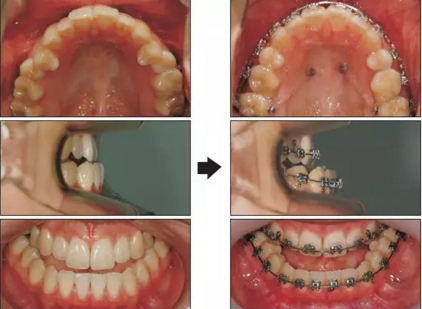

治療過(guò)程

拔除上頜第一前磨牙后,上牙上0.022-槽溝的托槽??紤]到上牙列關(guān)閉間隙需要的時(shí)間,下頜托槽在上牙初始排齊整平后安裝。在10個(gè)月的治療后,在雙側(cè)腭部各植入一枚8mm長(zhǎng)的支抗釘。用從支抗釘?shù)缴项M第二磨牙舌側(cè)扣的橡皮鏈壓低上頜磨牙。為了解決合平面傾斜,較左側(cè)更多地壓低右側(cè)磨牙。14個(gè)月的治療后,完全關(guān)閉了拔牙間隙,且上頜磨牙被壓低(Figure 3)。在術(shù)前正畸后,上下切牙角度達(dá)到正常范圍內(nèi)(upper occlusal plane to upper incisors, 59.1°; lower occlusal plane to lower incisors, 78.2°; upper occlusal plane to FH, 13.1°)。重新評(píng)估后確定可以進(jìn)行單頜手術(shù)獲得美觀面型。在手術(shù)10個(gè)月后移除矯治器??偟闹委煏r(shí)間為24個(gè)月。1周內(nèi)開始應(yīng)用Hawley保持器。

治療結(jié)果

患者獲得了顯著的面型改變。前突的頦部獲得了適當(dāng)?shù)暮笠?。下頜后退了大約10mm。頜骨矢狀向關(guān)系獲得了改善(Pog to N-perpendicular, −0.5 mm; ANB, −0.1°),面部不對(duì)稱問(wèn)題被糾正。獲得了I類尖牙關(guān)系和II類磨牙關(guān)系,獲得了理想的覆合覆蓋。獲得了一致的牙列中線。